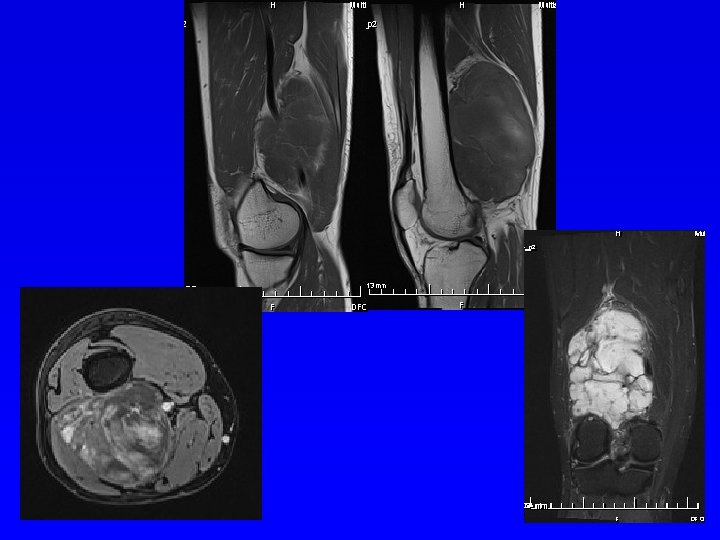

Magnetická rezonance MRI Silné magnetické pole Změny magnetických momentů spinu atomových jader s lichým atomovým číslem. Hyposignální- tmavé Hypersignální - světlé Nádory měkkých tkáně Onemocnění měkkých tkání Onemocnění páteře

MRI